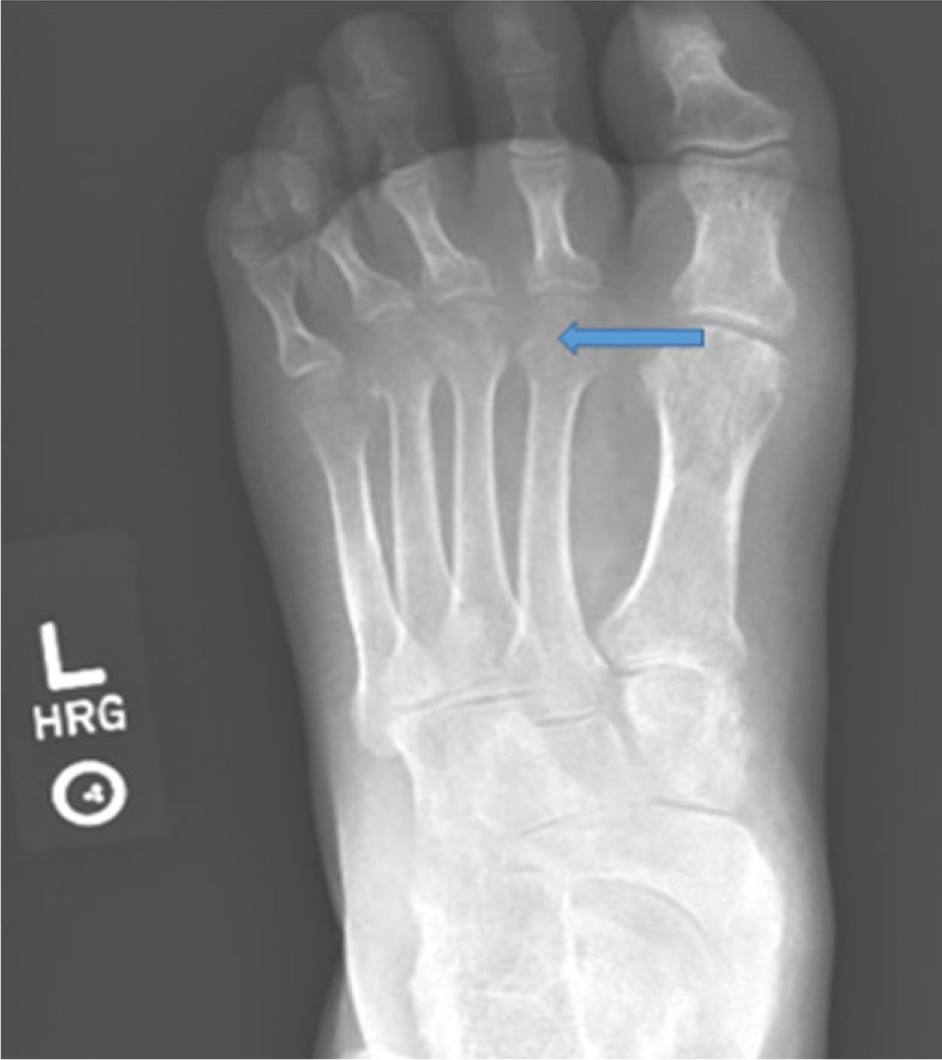

Foot X-ray showing metatarsal erosions.

Musculoskeletal association with HS has been reported. Most note an association with skin flares and that it tends to occur years after the onset of skin disease. Most reports are anecdotal. We identified one multicenter analysis. 18 The prevalence of spondyloarthopathy in HS patients was found to be 3.7% in this study. Arthritis was usually seronegative, insidious in onset, occurring 2 to 15 years after the appearance of skin lesions. It usually starts as an oligoarthritis, but may progress to asymmetric polyarthritis. Spondyloarthritis/sacroiliitis is the most common joint manifestation noted. 19 Joints affected includes knees followed by elbow, wrist, ankle, and shoulder. Radiographic findings include soft tissue swelling, periarticular osteoporosis, joint space narrowing, erosions, and periosteal new bone formation. 20 The arthritis can persist after a flare. Laboratory evaluation in these cases may reveal mild anemia, leukocytosis, and elevated erythrocyte sediment rate. ANA positivity has been reported. HLA-B27 is usually negative. HS with arthritis is also reported in association with pyoderma gangrenosum, recurrent urethritis, conjunctivitis, and xerophthalmia. 19 An entity called PAPASH syndrome pyogenic (inflammatory) arthritis, pyoderma gangrenosum, acne, hidradenitis suppurativa has been discussed in the literature. 21